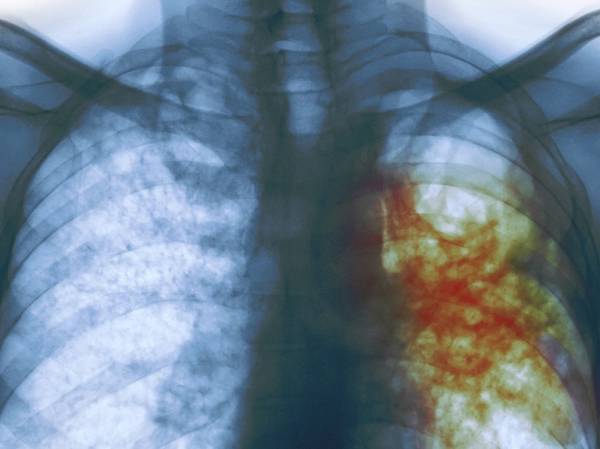

"Era muy frustrante, pero el último doctor particular que visité revisó mi radiografía y me dijo que probablemente era tuberculosis y ya en el Instituto Mexicano del Seguro Social (IMSS) me lo confirmaron", explica Gómez Coronado.

Castillo Rodal, quien forma parte del Departamento de Microbiología y Parasitología de la Facultad de Medicina de la UNAM, explica que 85 % de la tuberculosis es pulmonar y el resto se da en otros órganos o tejidos, y siempre ha sido un problema grave de salud.